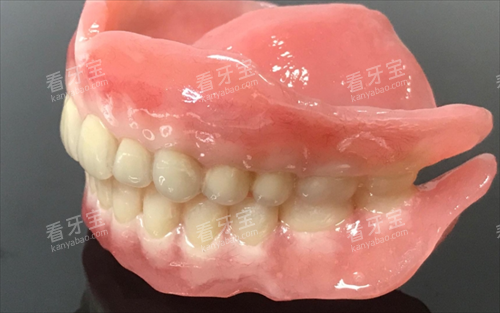

全口吸附性义齿是一种采用特殊设计的修复体,通过功能性印模技术和边缘封闭系统,在口腔内形成稳定的负压吸附力,使假牙能够紧密贴合牙槽骨黏膜表面。与传统活动假牙相比,它的稳固性和舒适度都有显著提升,外观也更接近自然牙齿。

基础树脂材质

这种材质的吸附性义齿价格相对亲民,适合预算有限、对咀嚼功能要求不是特别高的患者。但树脂基托容易老化,使用时需要特别注意保养。